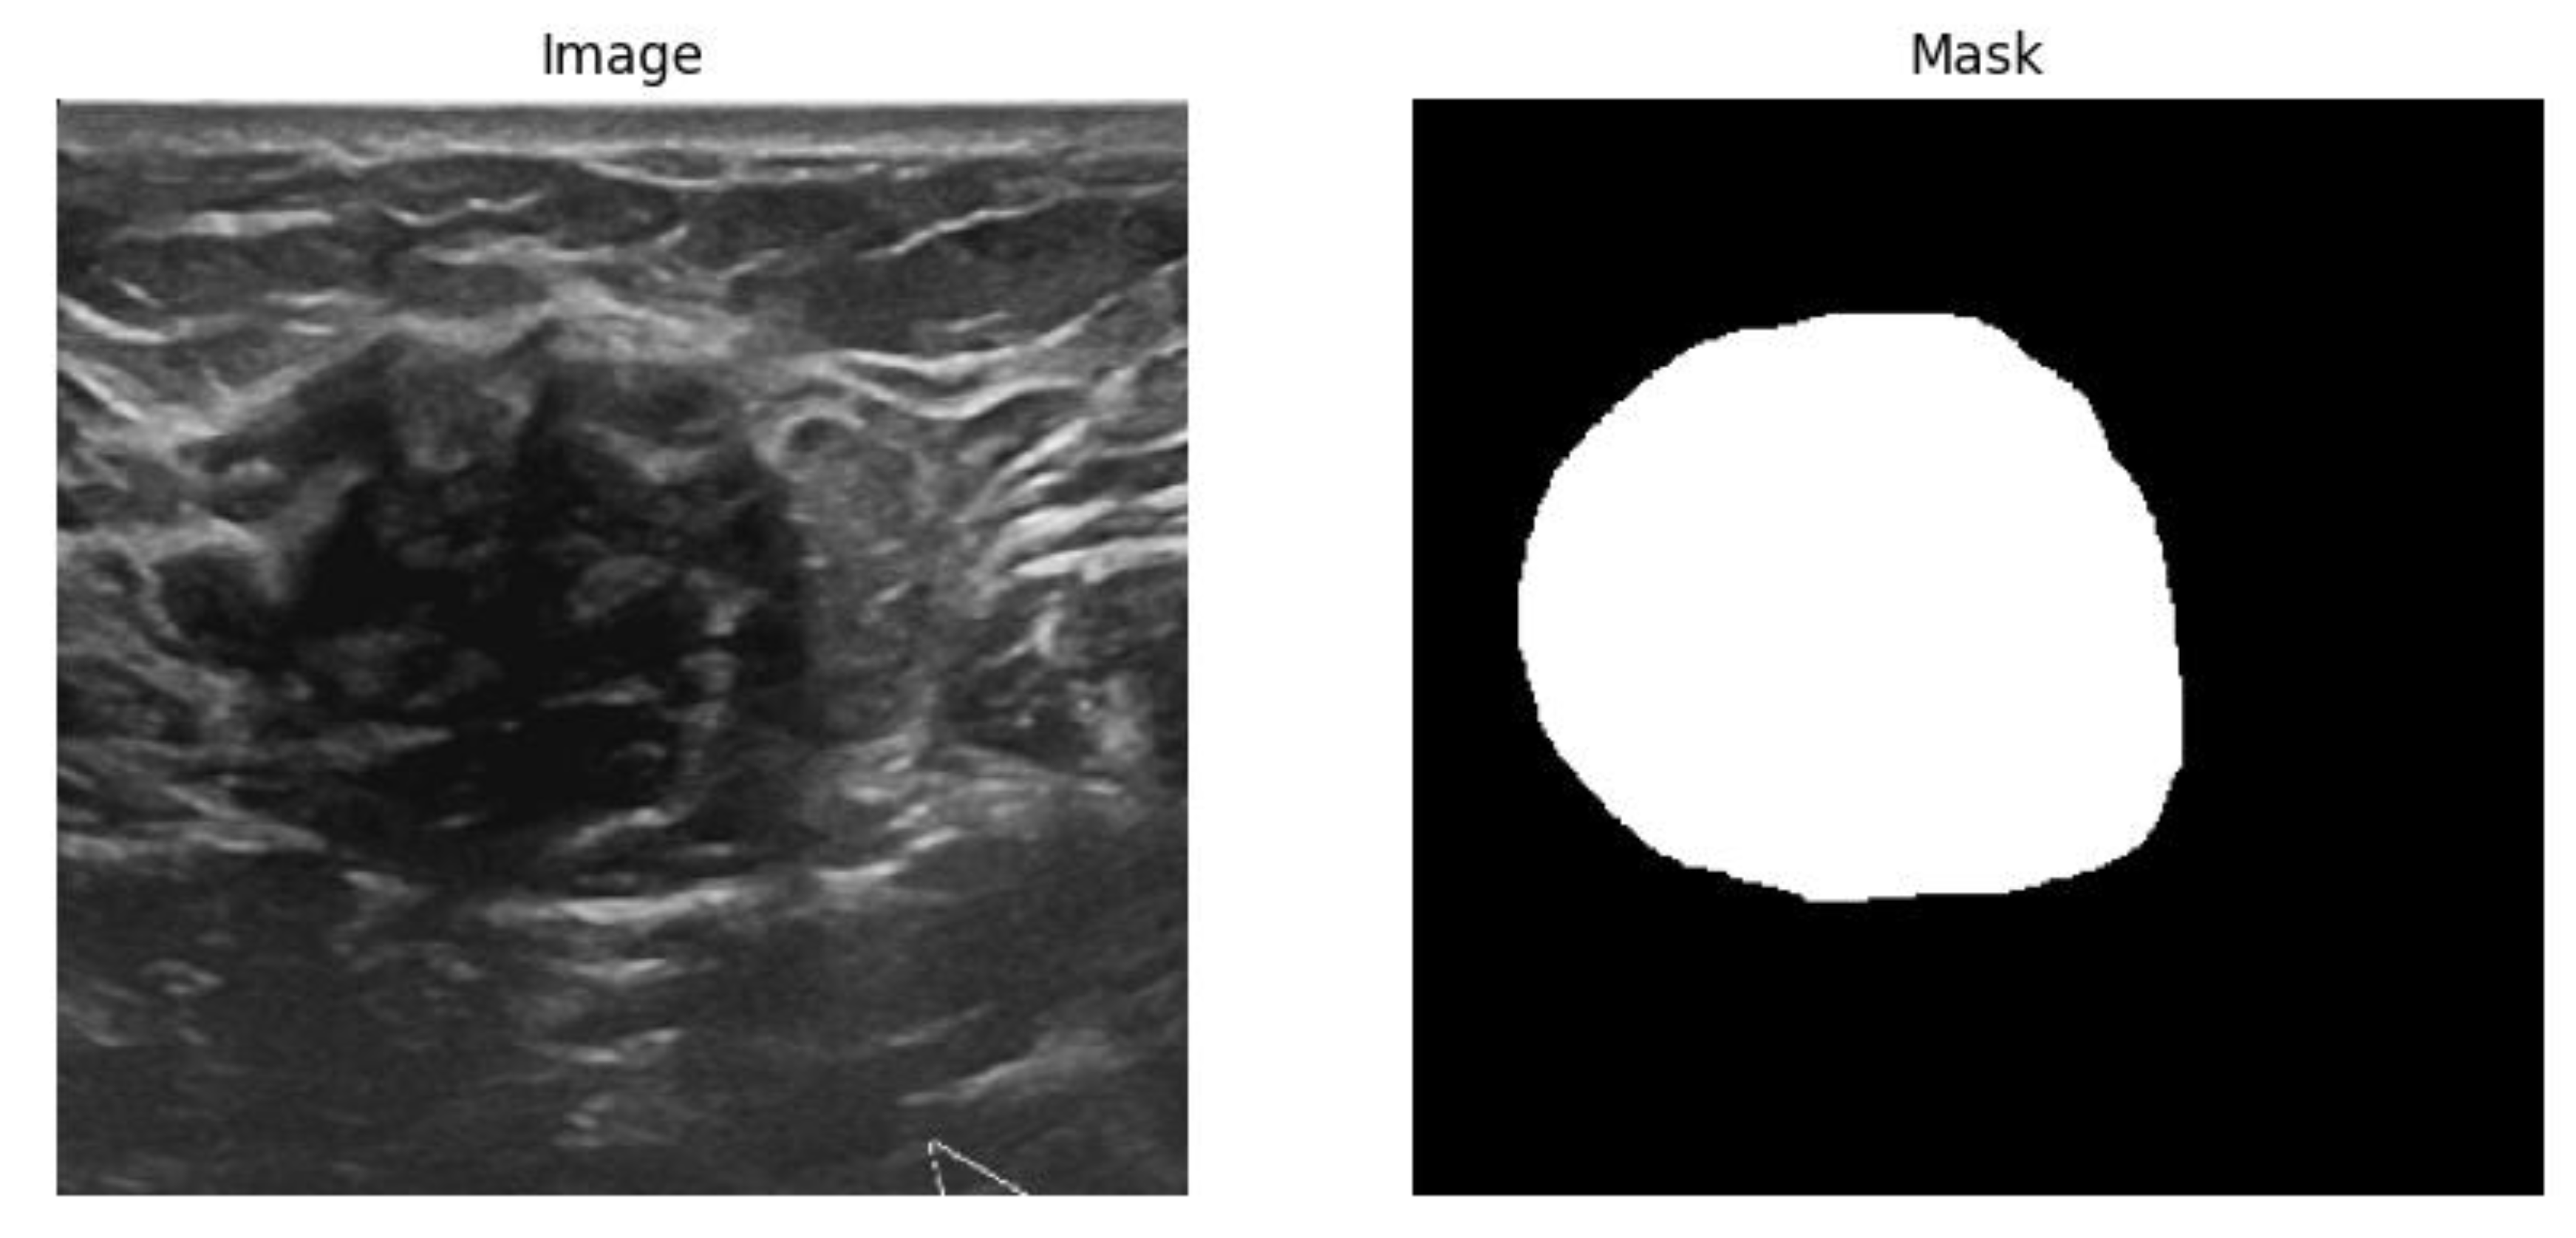

Figure 1. Sample image and mask pair data for image segmentation task.

BUSI dataset [34] was utilized for both segmentation and classification tasks in this study. Image segmentation and classification of the BUSI dataset remained a challenging task due to its poor image quality [26]. This dataset contains 780 images, categorized into three classes normal (132), benign (436), and malignant (210). Figure 2b) depicts the workflow of the breast cancer classifier development methodology. The first step of the development process is data preparation, in this step the dataset was divided into training, validation and test sets using an 80:10:10 split, and proportional representation of each class across the sets was ensured. In this study train and validation datasets were used in the training phase of the models and the test dataset was only used in the inference phase to evaluate the model performance and generalization on the unseen data. Table 2 shows the distribution of the images specific to each label. From the Table 2 it is evident that the dataset is an imbalanced dataset containing a greater number of instances with the “benign” label compared to “normal” or “malignant” samples.